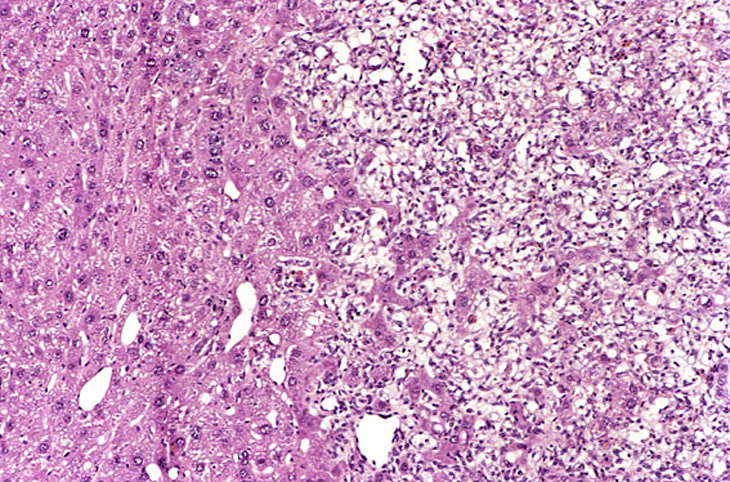

A relative discrete Ito cell tumor is present within this hepatic lobe; a higher magnification shows proliferation of stellate cells within the hepatic sinusoidal spaces.

This Ito cell tumor is comprised of a mixture of stellate cells and mature adipocytes.